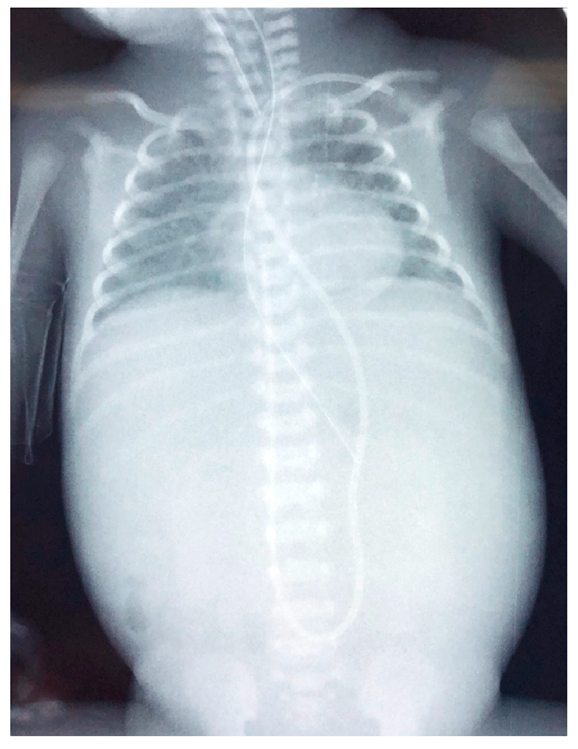

2.1. Case 1

2.2. Case 2

2.3. Case 3